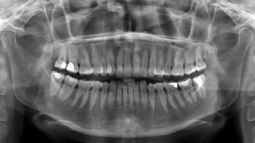

Ортопантомография: для чего она нужна?

Ортопантомография, или панорамная рентгенография челюстей, является важным инструментом в области стоматологии, позволяющим увидеть специалистам полную полости рта. Она предоставляет информацию о всех зубах, их корнях, состоянии зубных дуг, суставах и окружающих тканях. Это позволяет выявлять широкий спектр проблем, включая кариес, заболевания мягкого тканевого состава, кисты, опухоли и иные деформации.